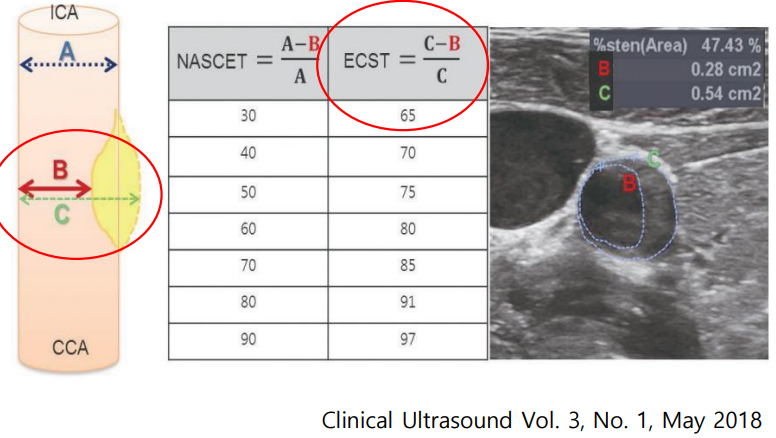

- 경동맥 초음파는 어떤 검사입니까?경동맥 에코는 심장에서 머리로 올라가는 동맥을 직접 초음파로 관찰하게 되는 것입니다.

심장에서 머리로 올라가는 동맥을 초음파로 보는 검사입니다① 혈관벽(Intima-mediathickness(IMT) 두께가 0.9mm이상으로 두꺼우거나 정상치의 75th percentile 이상이면 이상으로 간주합니다.② 혈관의 혈전(plaque)이 최근 혈관벽의 두께보다 더 중요한 의미를 가지는데 주변벽보다 50% 이상 두껍거나 1.5mm 이상 혈관벽의 두께를 나타내면 plaque가 있는 것으로 보입니다. 두께도 중요하지만 떨어져 가면 뇌졸중이기 때문에 혈전이 어떤 형태인지도 중요합니다.③ 혈관이 70% 이상 좁아진 경우에는 혈관 시술을 고려해야 합니다. stent를 넣거나…

- Plaque definition 1) focal wall thickening that is ≧ 50% greater than the surrounding vessel wall, 2) Focal region with an the surrounding vessel wall, 2) Focal region with an IMT

- * Plaque assessment 1) Plaque echogenicity, texture-homogeneous, heterogeneous-calcified, iso-echoic, hypo-echoic2) Doppler sonogra